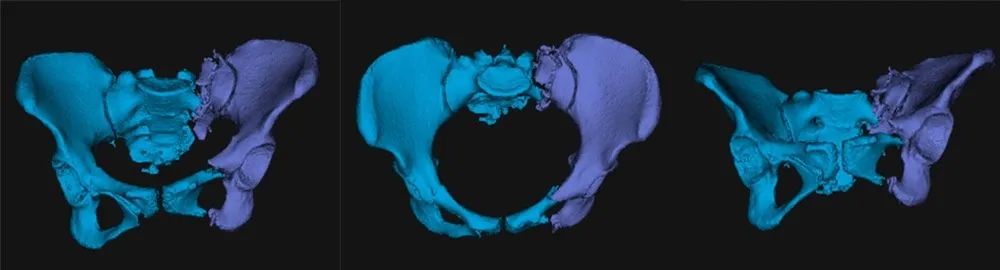

术前,手术团队进行了周密的准备,基于患者术前影像,借助基于AI与大数据的自动手术规划,将患者健侧肢体进行镜像配准,通过精细化自动分割与重建,实现个性化、定量化的复位规划。

图三:自动分割与重建

图四:人工智能复位规划